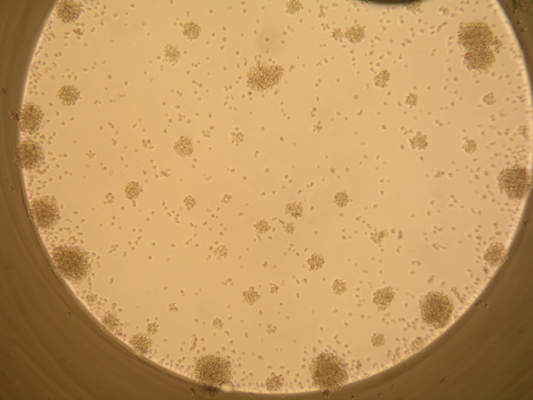

- Mikroskopischer Granulozytenaggregationstest (GAT)

- Mikroskopischer Granulozytenimmunfluoreszenztest (GIFT)